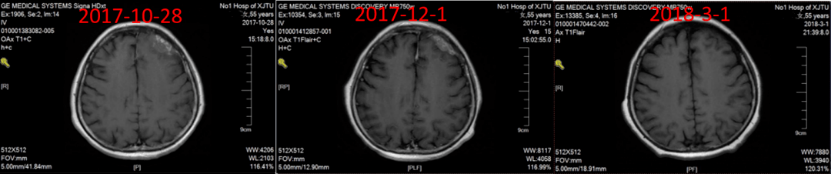

头颅CT(2017年10月28日)示:左额部颅板下不规则病灶,线状及环形强化,周围脑沟似见压迫征象,符合乳腺癌脑转移(图3)。

图3:头颅CT(2017年10月28日)

2017年10月25日~2018年2月22日,给予紫杉醇脂质体周疗×12+胸腔灌注×2+伽马刀立体定向治疗,疗效评价 部分缓解(PR)。2018年3月1日~2019年12月23日,给予氟维司群进行内分泌维持治疗,定期复查,病情稳定。

一线治疗PFS达到26个月,整体疗效评价PR(图4~7)。

图6:一线治疗期间随访颅脑CT

图7:一线维持治疗期间随访颅脑CT